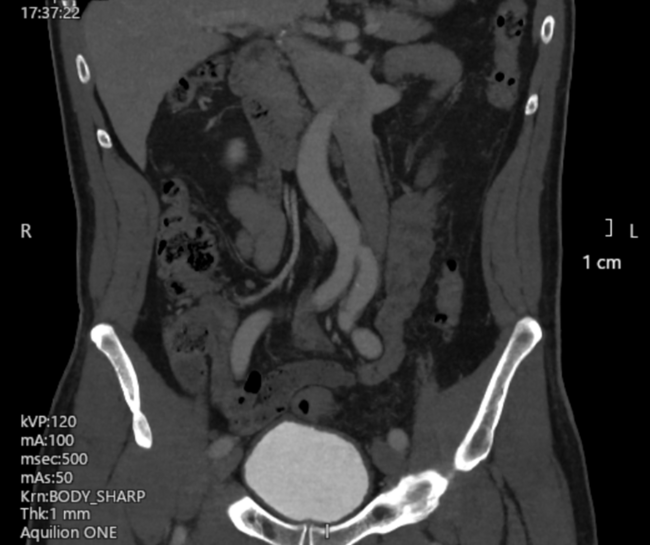

A computed tomography (CT) venogram of the inferior vena cava (IVC) and iliac and femoral veins was arranged. The scan showed a left-sided IVC, which “crossed over” to the right side at the renal vein level (Figure 2). The apparent filling defect was attributable to external compression of the right common iliac vein by the left iliac artery as it crossed to the left side (Figure 3).

Figure 2. (A-C) Three consecutive cuts of coronal plane images (anterior to posterior) from the patient’s computed tomography venogram. The left-sided inferior vena cava is marked with an asterisk. (B) The right iliac vein appeared to be compressed by the left iliac artery (arrow), which may explain the intraprocedural finding.